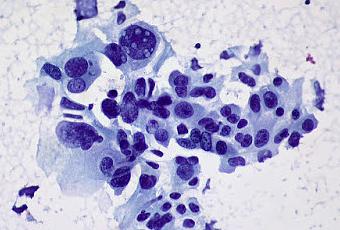

Cellules de cancer du poumon non à petites cellules. Ces cellules présentes pratiquement toutes les caractéristiques cardinales de la malignité: variation marquée de la dimension et de la forme du noyau, une chromatine irrégulièrement distribuée et de grands et importants pronucléi. Certaines cellules tumorales (...) étant positives pour p63 et négatives pour TTF1-alpha par immunohistochimie, le diagnostic final était: carcinome à cellules squameuses peu différenciées.

Source iconographique et légendaire: https://www.flickr.com/photos/euthman/5715460701